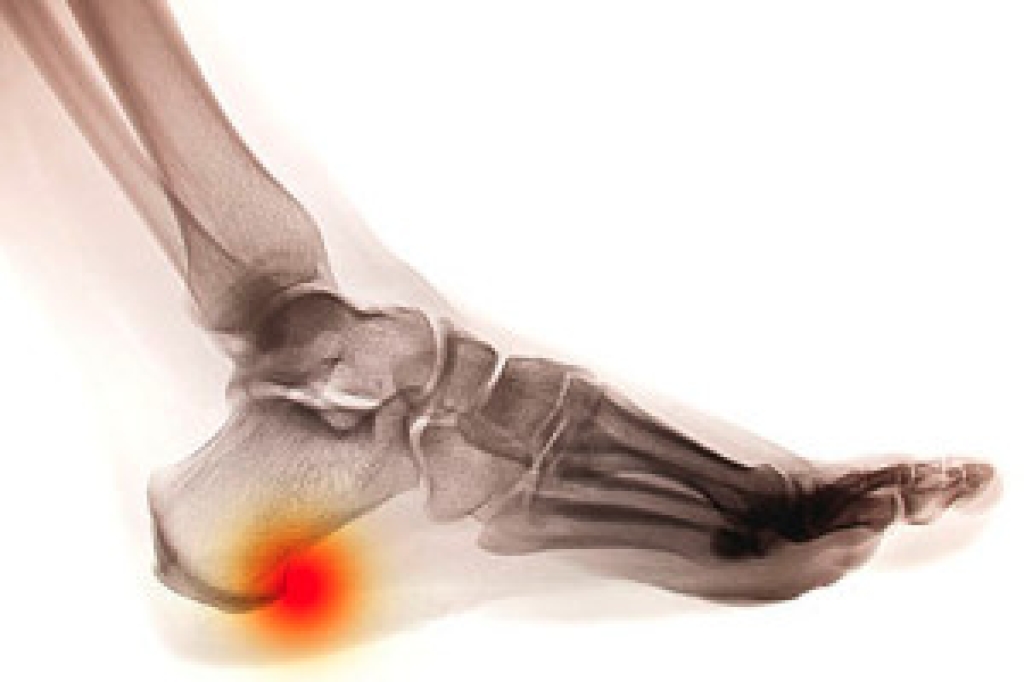

Many people have heel pain and show no other symptoms. This can indicate a heel spur has developed, and treatment is often sought for relief. A heel spur is defined as a bony growth that gradually forms on the bottom of the heel, and can come from excessive pressure the heels endure from being overweight, or if the plantar fascia becomes damaged. Wearing shoes that do not fit correctly may cause a heel spur to develop, in addition to having an abnormal foot structure. There are specific groups of people who may be prone to developing a heel spur. These can include runners, elderly people, diabetic patients, or people who have frequent gout attacks. People who have pain with a heel spur often notice there is tenderness surrounding the heel, and the affected foot and ankle may become swollen. Additionally, there may be sharp heel pain after rising in the morning. Effective prevention methods may consist of stretching the feet regularly, wearing insoles that can provide support, and maintaining a healthy weight. If you feel you have a heel spur, it is strongly urged that you consult with a podiatrist who can properly treat this condition.

Heel spurs are formed by calcium deposits on the back of the foot where the heel is. This can also be caused by small fragments of bone breaking off one section of the foot, attaching onto the back of the foot. Heel spurs can also be bone growth on the back of the foot and may grow in the direction of the arch of the foot.

The pain associated with spurs is often because of weight placed on the feet. When someone is walking, their entire weight is concentrated on the feet. Bone spurs then have the tendency to affect other bones and tissues around the foot. As the pain continues, the feet will become tender and sensitive over time.